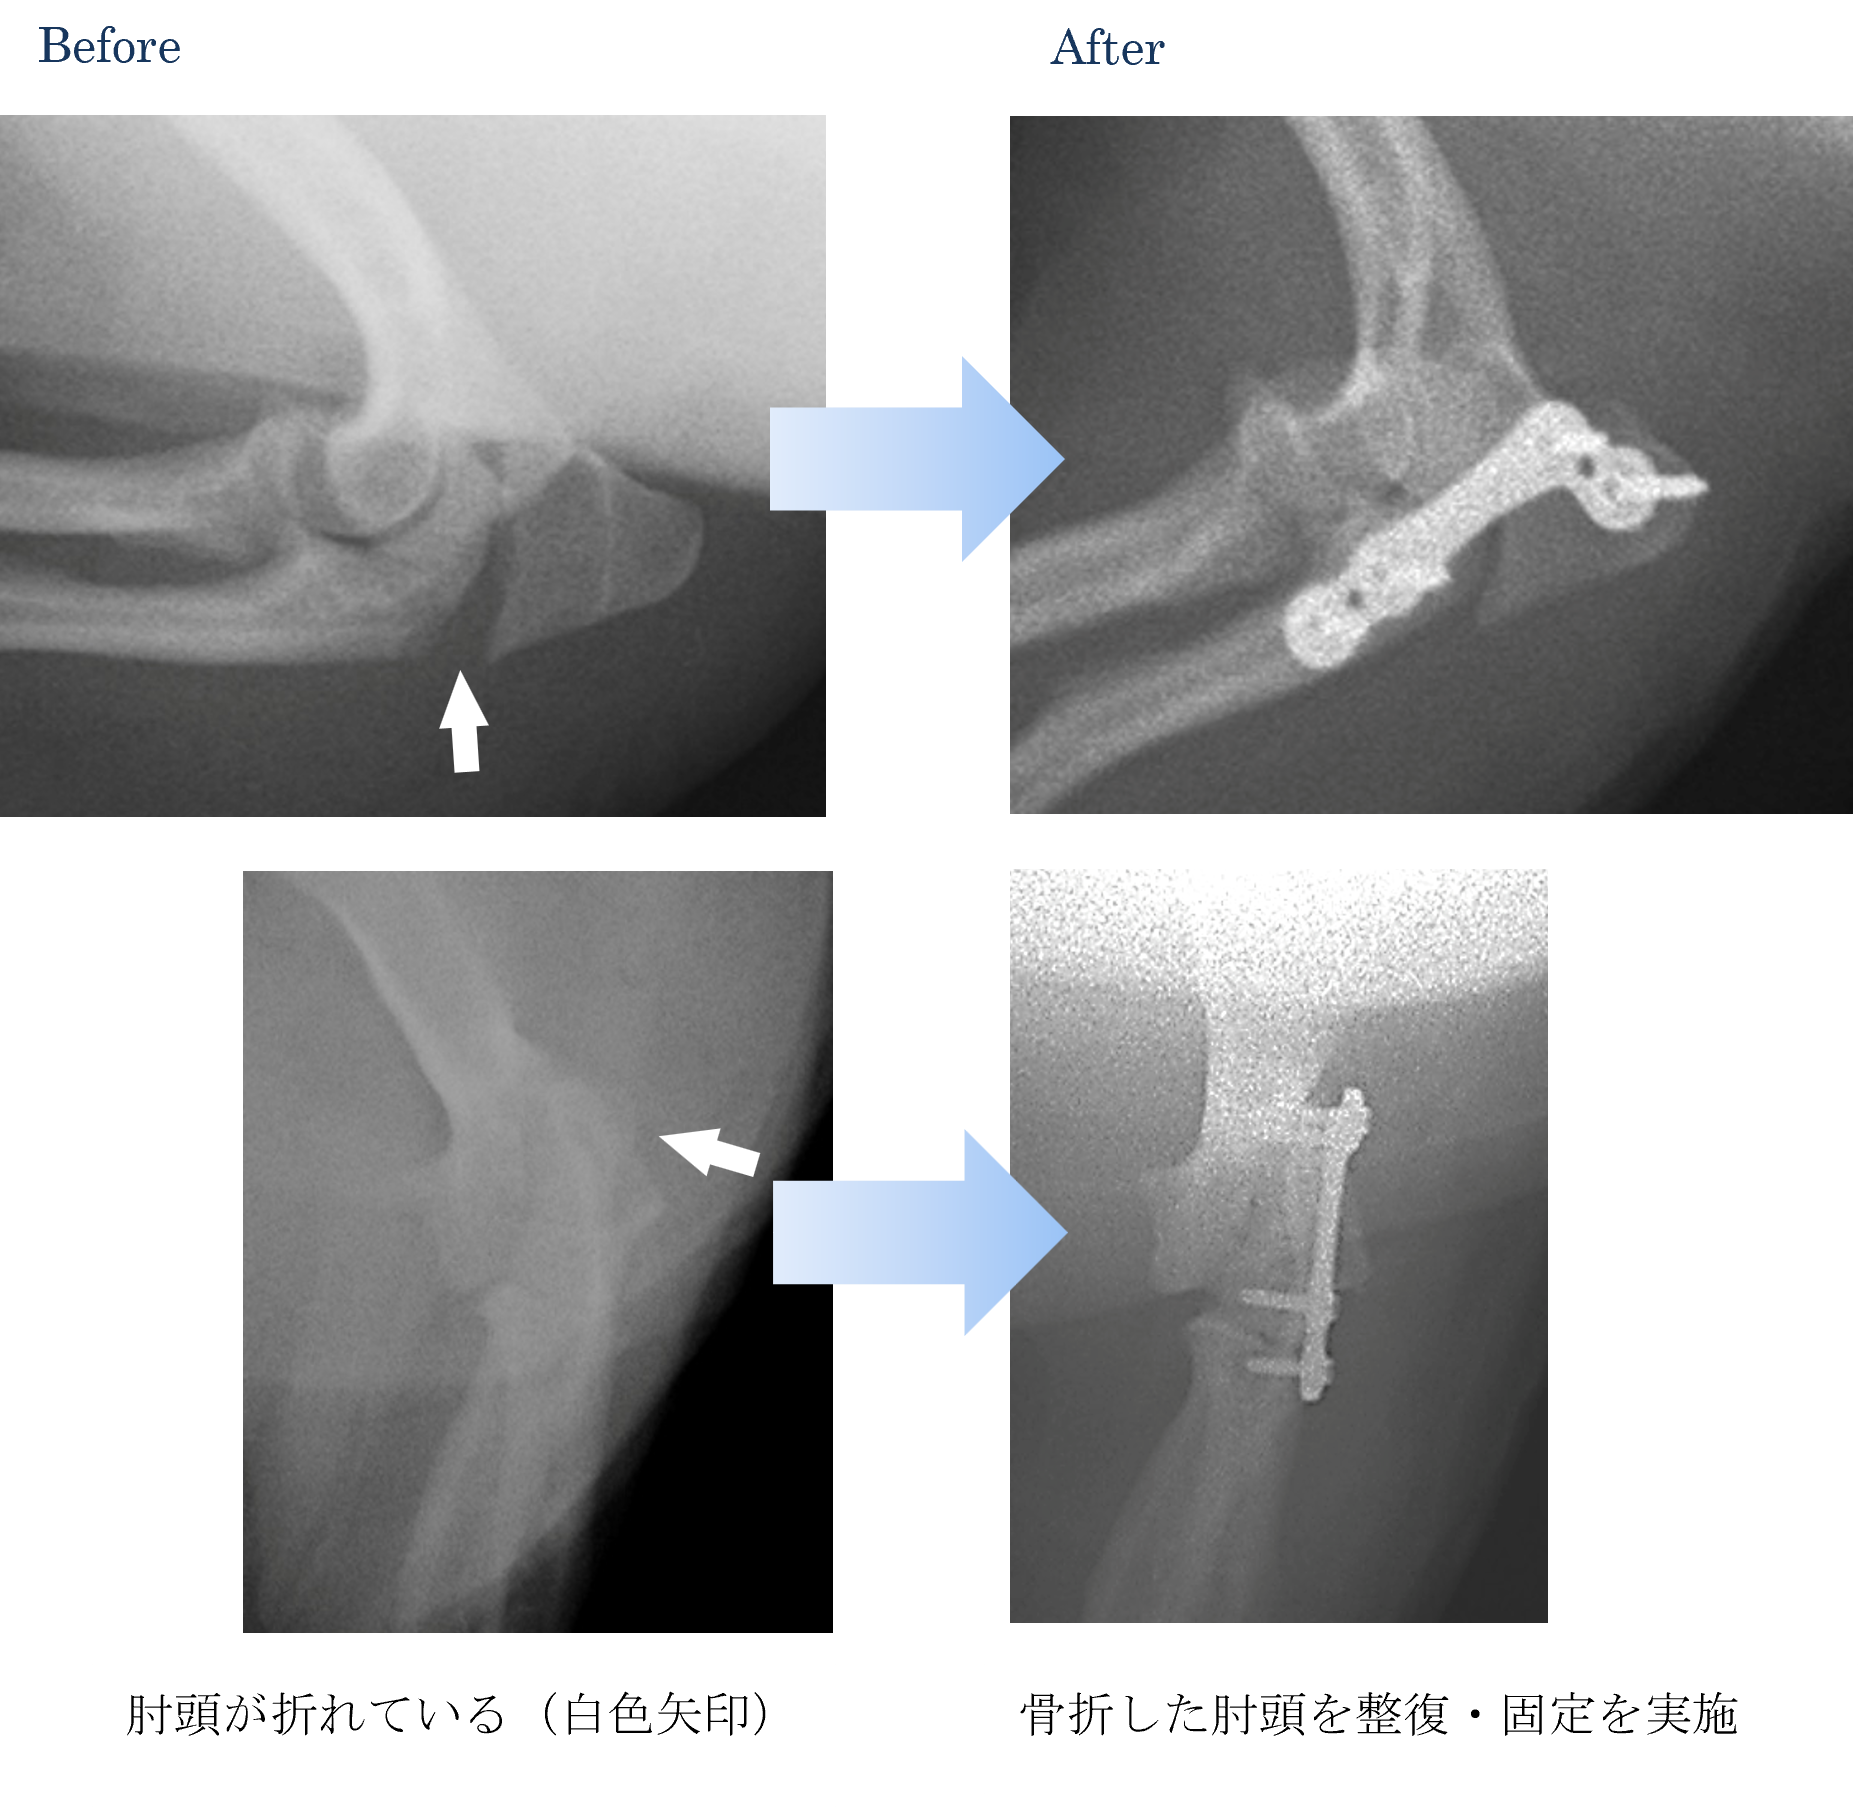

同居の犬ちゃんに咬まれてから痛がって前足の挙上がみられる【肘頭骨折】

各種検査より、肘頭の骨折と診断しました。

ご家族と相談して手術で整復して固定を実施することになりました。

手術後は以前と同じように走ったり遊んだりすることができるようになりました。